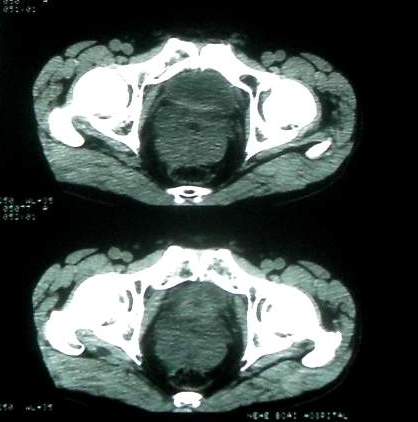

男 60岁,下腹部肿块半年余

前列腺肥大,密度不均。伴盆腔实性肿块。考虑前列腺癌伴盆腔转移。建议增强扫描。

考虑来源于肠道的肿瘤,乙状结肠?询问排便情况

盆腔恶性占位,间质瘤可能性大

乙状结肠间质瘤

盆腔恶性占位,间质瘤可能性大。

病理结果:肠系膜肉瘤

病灶形态不规则,偏心性裂隙样坏死,支持恶性病变。来源不好定。感谢反馈结果--肠系膜肉瘤。